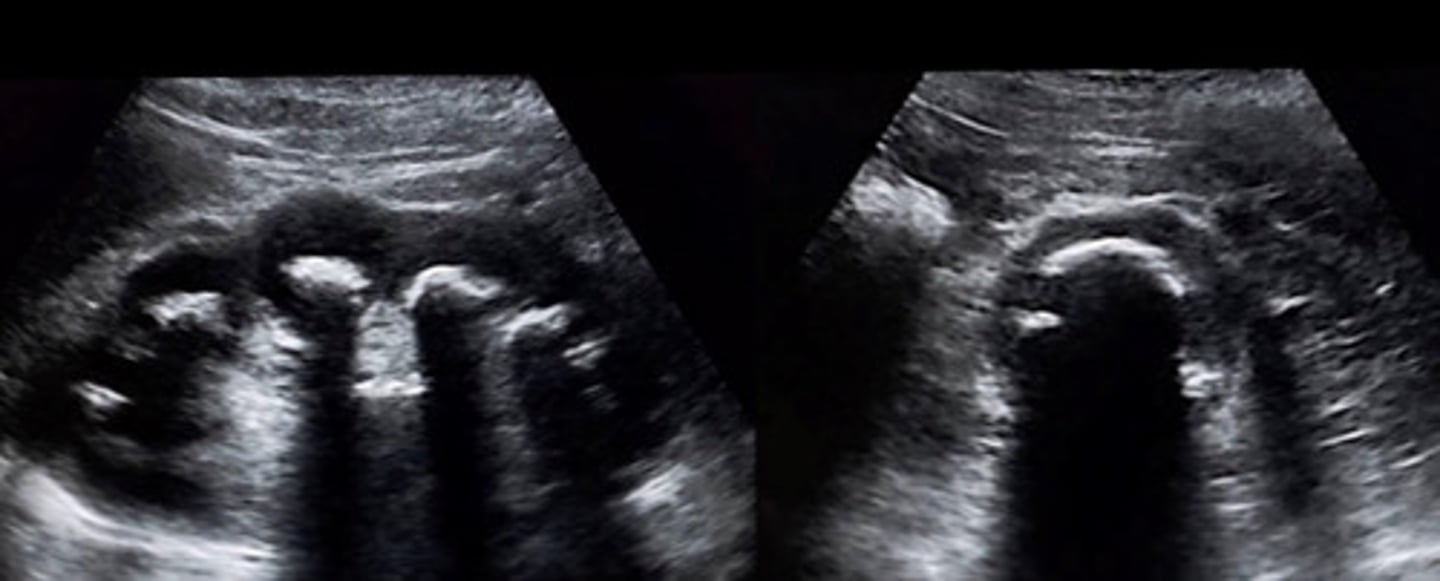

Grade 1 hydro

What does this image show

Separation of entire central sinus and club calyces

Describe the appearance of grade 2 hydro

Pelvis, minor and major calyceal system

What is dilated in the case of grade 2 hydro

Rounded like the slubs in a deck of cards (can see an outline of the calyceal system)

Describe the appearance of clubbed calyces

Grade 2 hydro